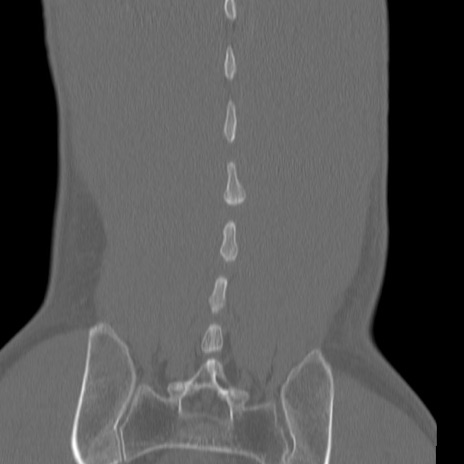

症例3 腰椎CT(冠状断像)

【症例】30歳代男性

【主訴】腰痛

【現病歴】本日旅行先で観光中に、友人と衝突し転倒し受傷。

【身体所見】麻痺なし、右下腿内側前面外側、左下腿内側に知覚鈍麻・しびれ

異常所見と診断は?

腰椎CT